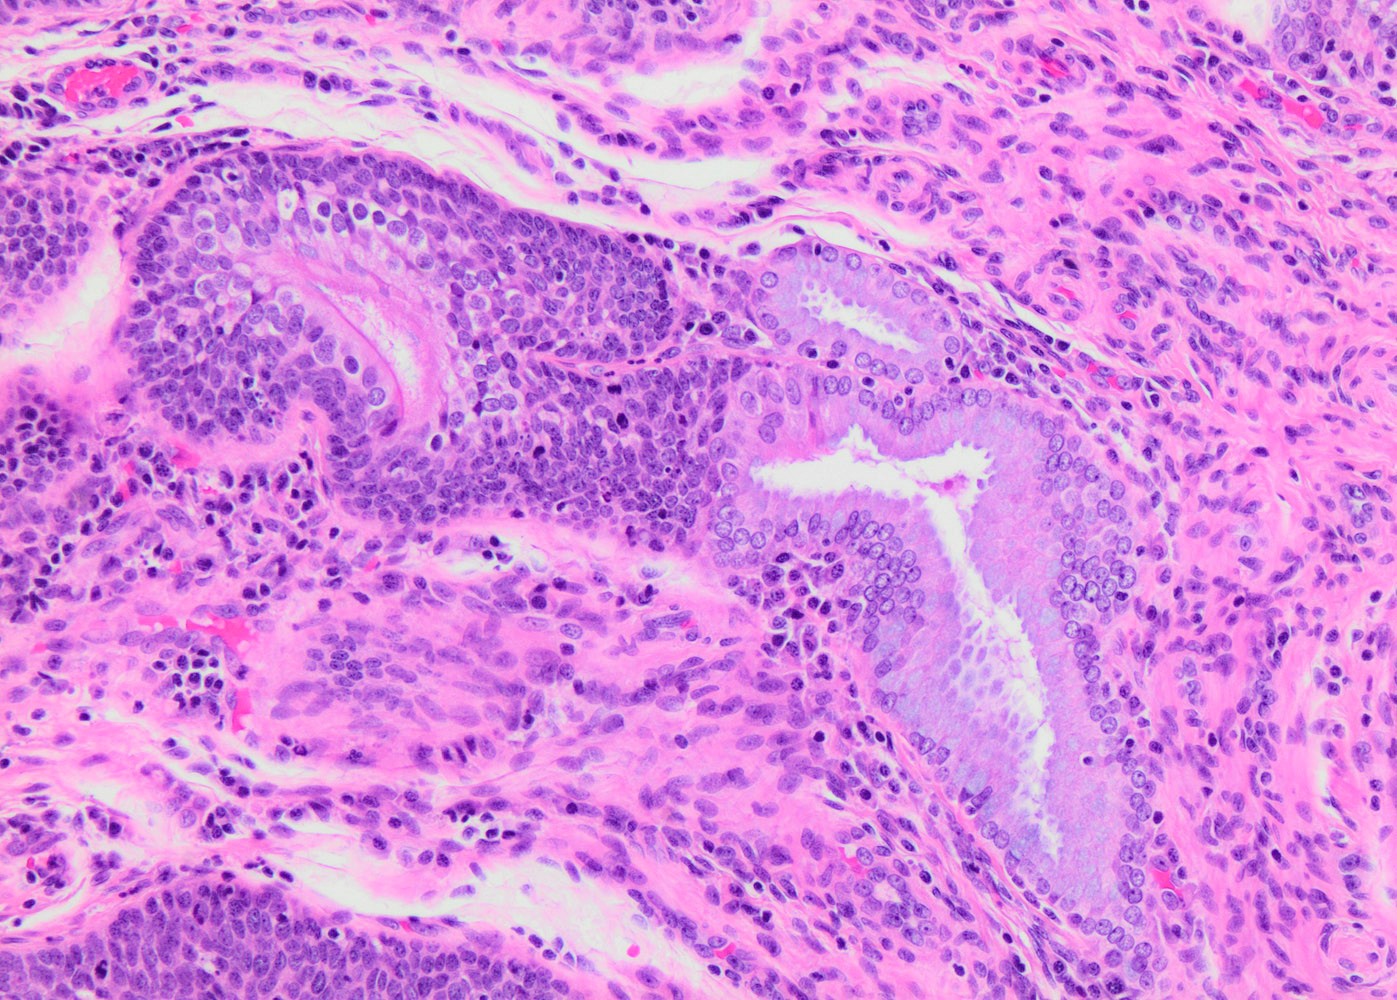

- Conventional / classic pattern: full thickness nuclear abnormalities (hyperchromasia, coarse chromatin, irregular nuclear contours and inconspicuous nucleoli), high N/C ratio in at least lower two - thirds of epithelium

- CIN II: cytoplasmic maturation in the upper third of mucosa

- CIN III: full thickness basal / parabasal type, no maturation difference across layers

- Increased mitotic activity with atypical mitoses

- Other patterns:

- Thin HSIL: < 10 cells thick; can mimic atrophy; usually focal and coexists with conventional HSIL (Histopathology 2019;75:405, Int J Gynecol Pathol 2017;36:71)

- Keratinizing HSIL: superficial keratinization without koilocytosis

- Papillary HSIL: lining endocervical papillae

- Pleomorphic HSIL: focal bizarre nuclear changes / multinucleation (Pathology 2017;49:465)

- May present as small metaplastic type cells mimicking immature metaplastic epithelium (Int J Gynecol Pathol 2007;26:180, Am J Surg Pathol 2014;38:470)

Microscopic (histologic) images

Contributed by Khaled J. Alkhateeb, M.B.B.S.